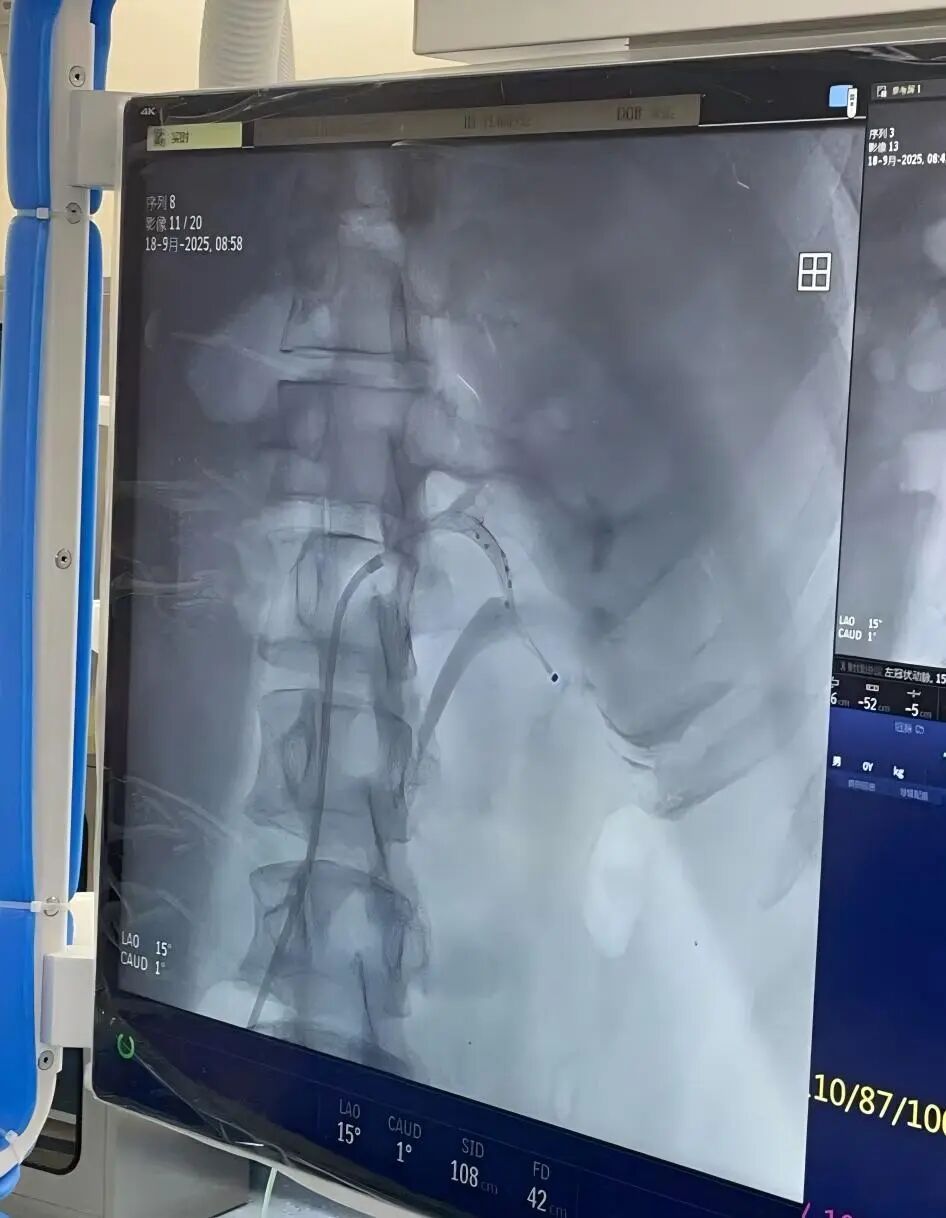

瑞金医院嘉定院区刘常远主治医师接诊后将其收入病房,在陈歆主任指导下对张先生进行了全面细致的评估,重点在于筛查继发性高血压及评估靶器官损害情况,最终诊断原发性高血压,结合患者肾动脉情况明确其符合RDN手术指征,完善术前检查后为其制定了周密的手术方案。手术当天,由许建忠主任作为主刀医师,刘常远主治医师、李明春主治医师作为助手,凭借娴熟的介入技术,将肾动脉消融导管精准送达双侧肾动脉及副肾动脉,通过射频能量对双侧肾动脉交感神经进行消融。整个手术历时约1.5个小时,共消融56个点位,全程患者无明显不适,术后在护理团队的精心照护下,患者生命体征平稳,感觉良好。